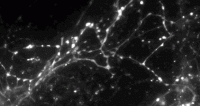

To obtain a detailed view of synaptic activity, Sulzer’s team collaborated with the laboratory of Dalibor Sames, PhD, associate professor of chemistry at Columbia, to develop a novel compound called fluorescent false neurotransmitter 200 (FFN200). When added to brain tissue or nerve cells from mice, FFN200 mimics the brain’s natural neurotransmitters and allows researchers to spy on chemical messaging in action.

Using a fluorescence microscope, the researchers were able to view the release and reuptake of dopamine—a neurotransmitter involved in motor learning, habit formation, and reward-seeking behavior—in individual synapses. When all the neurons were electrically stimulated in a sample of brain tissue, the researchers expected all the synapses to release dopamine. Instead, they found that less than 20 percent of dopaminergic synapses were active following a pulse of electricity.